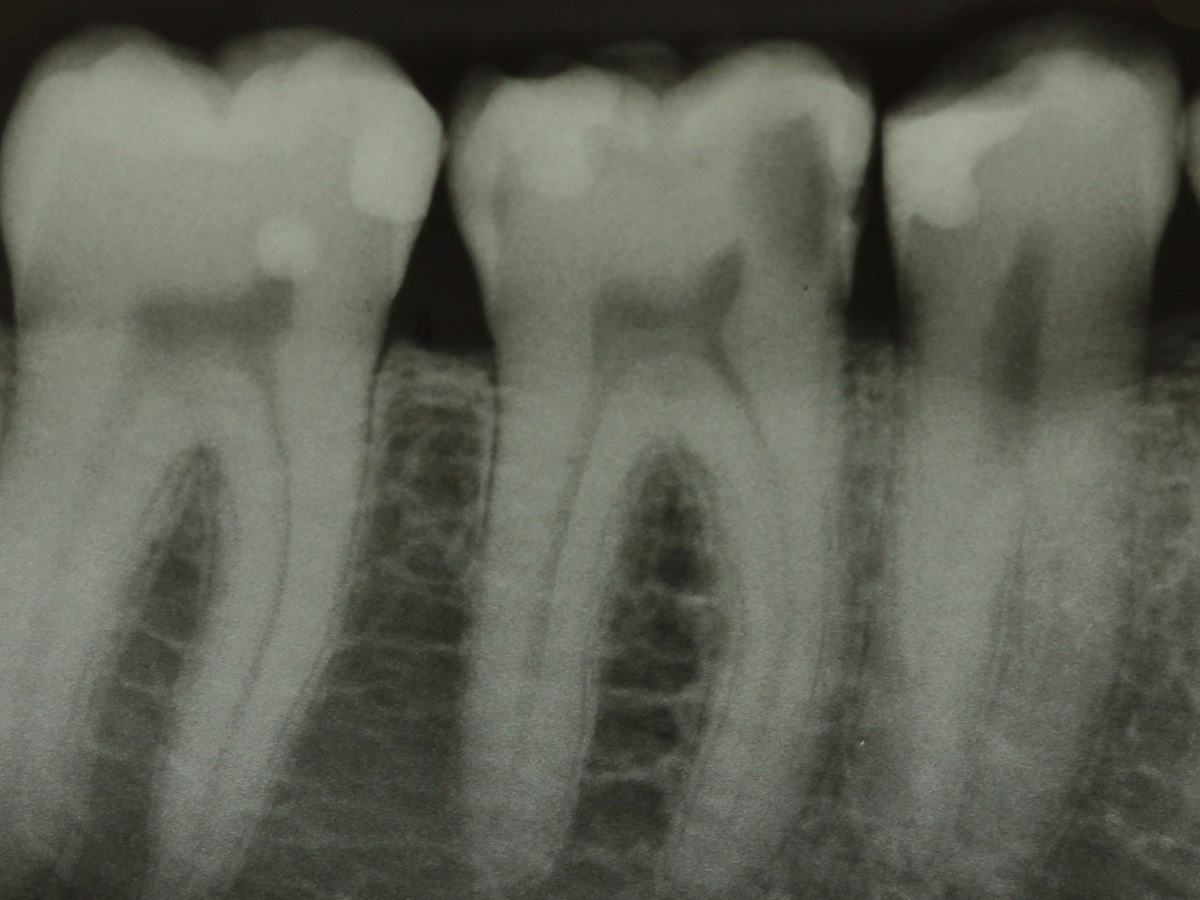

Abbildung 1a

Bissflügelröntgenaufnahme